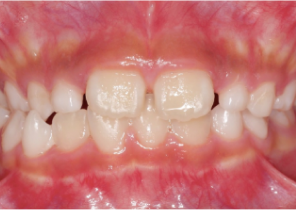

Opis przypadku nr 1

10 lat, 0 miesięcy, 18 etapów leczenia Invisalign Palatal Expander

Dzięki uprzejmości dr Sandry Khong Tai

Przed ekspansją eInvisalign Palatal Expander

Po ekspansji Invisalign Palatal Expander

Po leczeniu Invisalign First